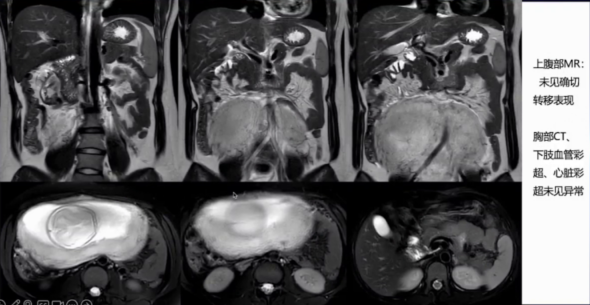

超声:胎儿大小符合孕周,估计体重530g。右侧卵巢内膜样囊肿可能(4cm);余肝胆胰脾、双肾输尿管、下肢深静脉超声未见明显异常。

胸部CT:未见明显异常。

盆腔MRI:宫颈外口异常信号灶2.4cm×1.1cm,考虑MT。双侧附件内膜样囊肿可能(右4cm,左2cm)

孕妇化疗后不良反应较小,血象三系基本正常,肿瘤标志物无明显异常,宫颈外口病灶有缩小趋势。